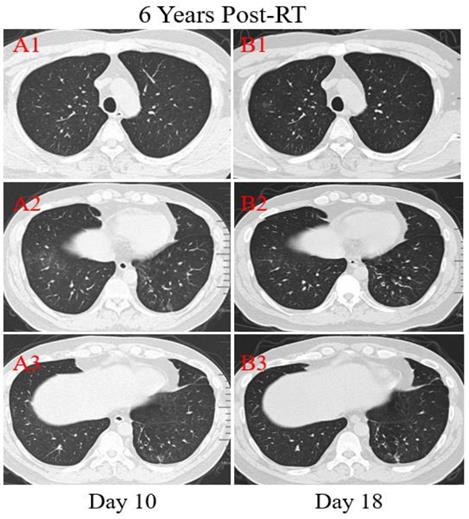

Patient 1: A 53-year-old male was diagnosed with middle and lower esophageal squamous cell carcinoma with multiple bone metastases staged with T4aN2M1 and began to receive palliative concurrent chemoradiotherapy on September 29, 2016, and admitted to the hospital on January 28, 2020. He had sputum production and cough of more than ten days duration, and a little bit hemoptysis of two days duration. He also felt fatigued, chest distress, vomiting after eating, but no fever. He was neither from the infected area nor contacted with infected peoples. The physical examination revealed coarse breath sounds during auscultation, and laboratory studies showed normal leukocyte, but lymphopenia and serious thrombocytopenia. Also, markly elevated concentrations of D-dimer, Procalcitonin (PCT), C-reactive protein (CRP), and N-terminal-pro hormone brain-type natriuretic peptide (NT-BNP) were observed at admission. Results of serial CT scans showed pericardial effusion, multiple enlarged lymph nodes in the mediastinum, scattered, multiple, similar round thin wall/no wall transparent areas (Figure 2. A2, B2, C3), smooth or nodular interlobular septal thickening (Figure 2. A1, B1), and multiple nodules in the dorsal segment of the lower lobe of both lungs with spotted calcifications and adjacent pleural thickening (Figure 2. A2, A3). Above lung lesions were approximately the same as before. Moreover, compared with the previous CT scan 12.6 months before, chest CT images performed at the 10th day after symptom onset showed the obviously progressive lung lesions including patchy areas of consolidation co-existed with ground-glass opacities (Figure 2. A3), or linear scarring with discrete consolidation (Figure 2. A2), air bronchograms (Figure 2. A1), and irregular intralobular or interlobular septal thickening (Figure 2. A1-3) in the lower lobes of both lungs adjacent to the mediastinum conforming completely to the irradiated area. It was suggested the possibility of RILI, interstitial pneumonia or viral pneumonia. After 3 days of anti-infective therapy with tazocin, moxifloxacin, and arbidol, combined with aggressive supportive care, follow-up CT demonstrated partial improvement (Figure 2. B1) but primarily increment in the extent and density of lung lesions (Figure 2. B2, B3), and continued segmental consolidations and atelectasis were observed in the lower lobe of both lungs (Figure 2. B3). Repeated three times of swab nucleic acid tests for the COVID-19 were negative, and he ultimately was excluded. Afterward, the patient was transferred to the Department of Oncology to continue treatment to reduce the burden of the frontier department.

Transverse thin-section serial CT scans from a 53-year-old male with suspected COVID-19 pneumonia. Serial CT scans showed pericardial effusion, multiple enlarged lymph nodes in the mediastinum, scattered, multiple, similar round thin wall/no wall transparent areas (A2, B2, C3), smooth or nodular interlobular septal thickening (A1, B1), and multiple nodules in the dorsal segment of the lower lobe of both lungs with spotted calcifications and adjacent pleural thickening (A2, A3). Chest CT images performed at the 10th day after symptom onset showed patchy areas of consolidation co-existed with ground-glass opacities (A3), or linear scarring with discrete consolidation (A2), air bronchograms (A1), and irregular intralobular or interlobular septal thickening (A1-3, A3). Follow-up CT at the 13rd day demonstrated partial improvement (B1) but primarily increment in the extent and density (B2, B3), continued segmental consolidations and atelectasis in the lower lobe of both lungs (B3).